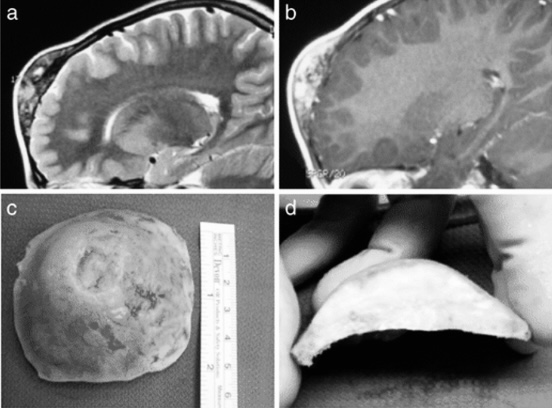

患者存在双侧视乳头水肿,但无其他局灶性神经功能缺损。全部...

手术方案与体位的确定基于两处病变均引发症状,因此选择单一...